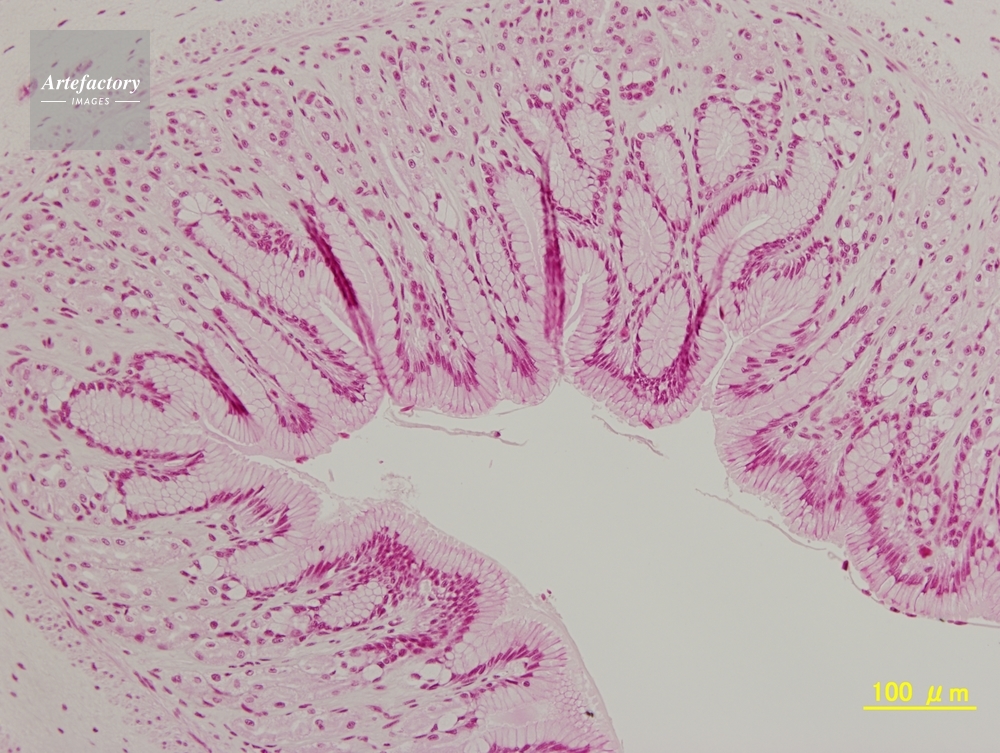

| 作品タイトル | カエル,胃 | モデルリリース | なし | |

| 作家 | OLYMPUS CORPORATION Technolab | プロパティリリース | なし | |